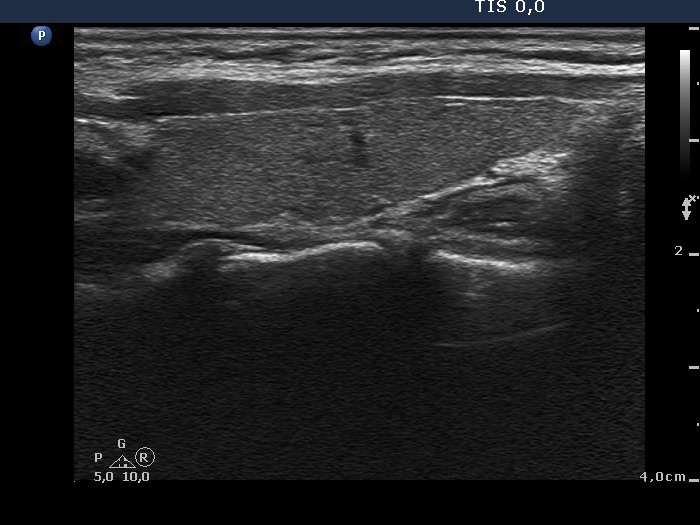

Consecutively operated patients with autoimmune thyroid disease - case 36 (conp 061) (ultrasonographic picture 8)

Left lobe, longitudinal scan.